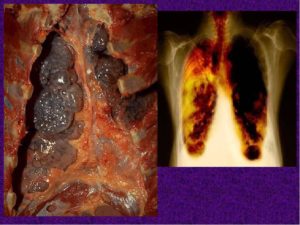

Буллезная форма эмфиземы лёгких (код по МКБ 10 – J 43.9) представляет собой патологию дыхания, характеризующуюся чрезмерным расширением и разрушением стенок воздушных пузырьков (альвеол).

В результате истончения и разрушения альвеолярных перегородок в лёгких образуются участки скопления воздуха – эмфизематозные буллы от 1 до 10 см в диаметре.

Буллы чаще располагаются в области верхних долей лёгких.

Рентген выявляет повышение прозрачности и воздушности лёгочных полей, заниженный купол диафрагмы, расширение межреберных пространств, усиление рисунка.

Диагноз подтверждается наличием на снимке кист в верхушечных сегментах лёгкого.

На ранних стадиях более информативным является метод компьютерной томографии. При проведении КТ картина заболевания наиболее ясная: зоны повышенной деструкции отчётливо видны.

Буллезная эмфизема легкого – это локальные изменения легочной ткани, характеризующиеся деструкцией альвеолярных перегородок и формированием воздушных кист диаметром более 1 см (булл). При неосложненном течении буллезной эмфиземы легких симптомы могут отсутствовать вплоть до возникновения спонтанного пневмоторакса.

Диагностическое подтверждение буллезной эмфиземы легких достигается с помощью рентгенографии, КТ высокого разрешения, сцинтиграфии, торакоскопии.

В то же время, возможности лучевой диагностики существенно расширяет внедрение в практику КТ высокого разрешения. На томограммах буллы определяются как тонкостенные полости с четкими и ровными контурами. При сомнительном диагнозе удостовериться в наличии булл позволяет диагностическая торакоскопия.